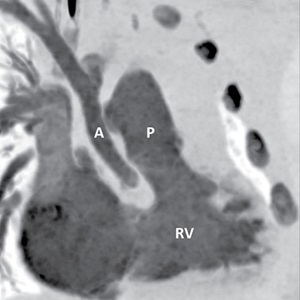

Dr. Bardo remembers a 10-year-old patient who came into the hospital with hypoplastic left heart syndrome. Using a 3D model of the child’s heart, Dr. Bardo sat down with the patient and her mother to explain the anatomy and what the disease looked like.

“I remember the mother looking at me and saying, ‘After all these years, this is the first time I really understand what is wrong with my daughter’s heart,” recalls Dr. Bardo. “It was then that I realized the power 3D printing has to truly personalize patient care.”